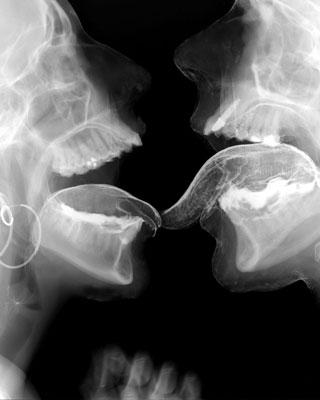

MudamSérie 9 muses (2001) : série de vitraux réalisés avec des plaques d'imagerie médicale aux rayons X eux-mêmes « X » puisqu'il s'agit de scènes pornographiques (fellation, coït).

Thalia, 2001-2002 (steel, X-rays, lead, glass)

Erato, 2001-2002

fuck 2000, 2001